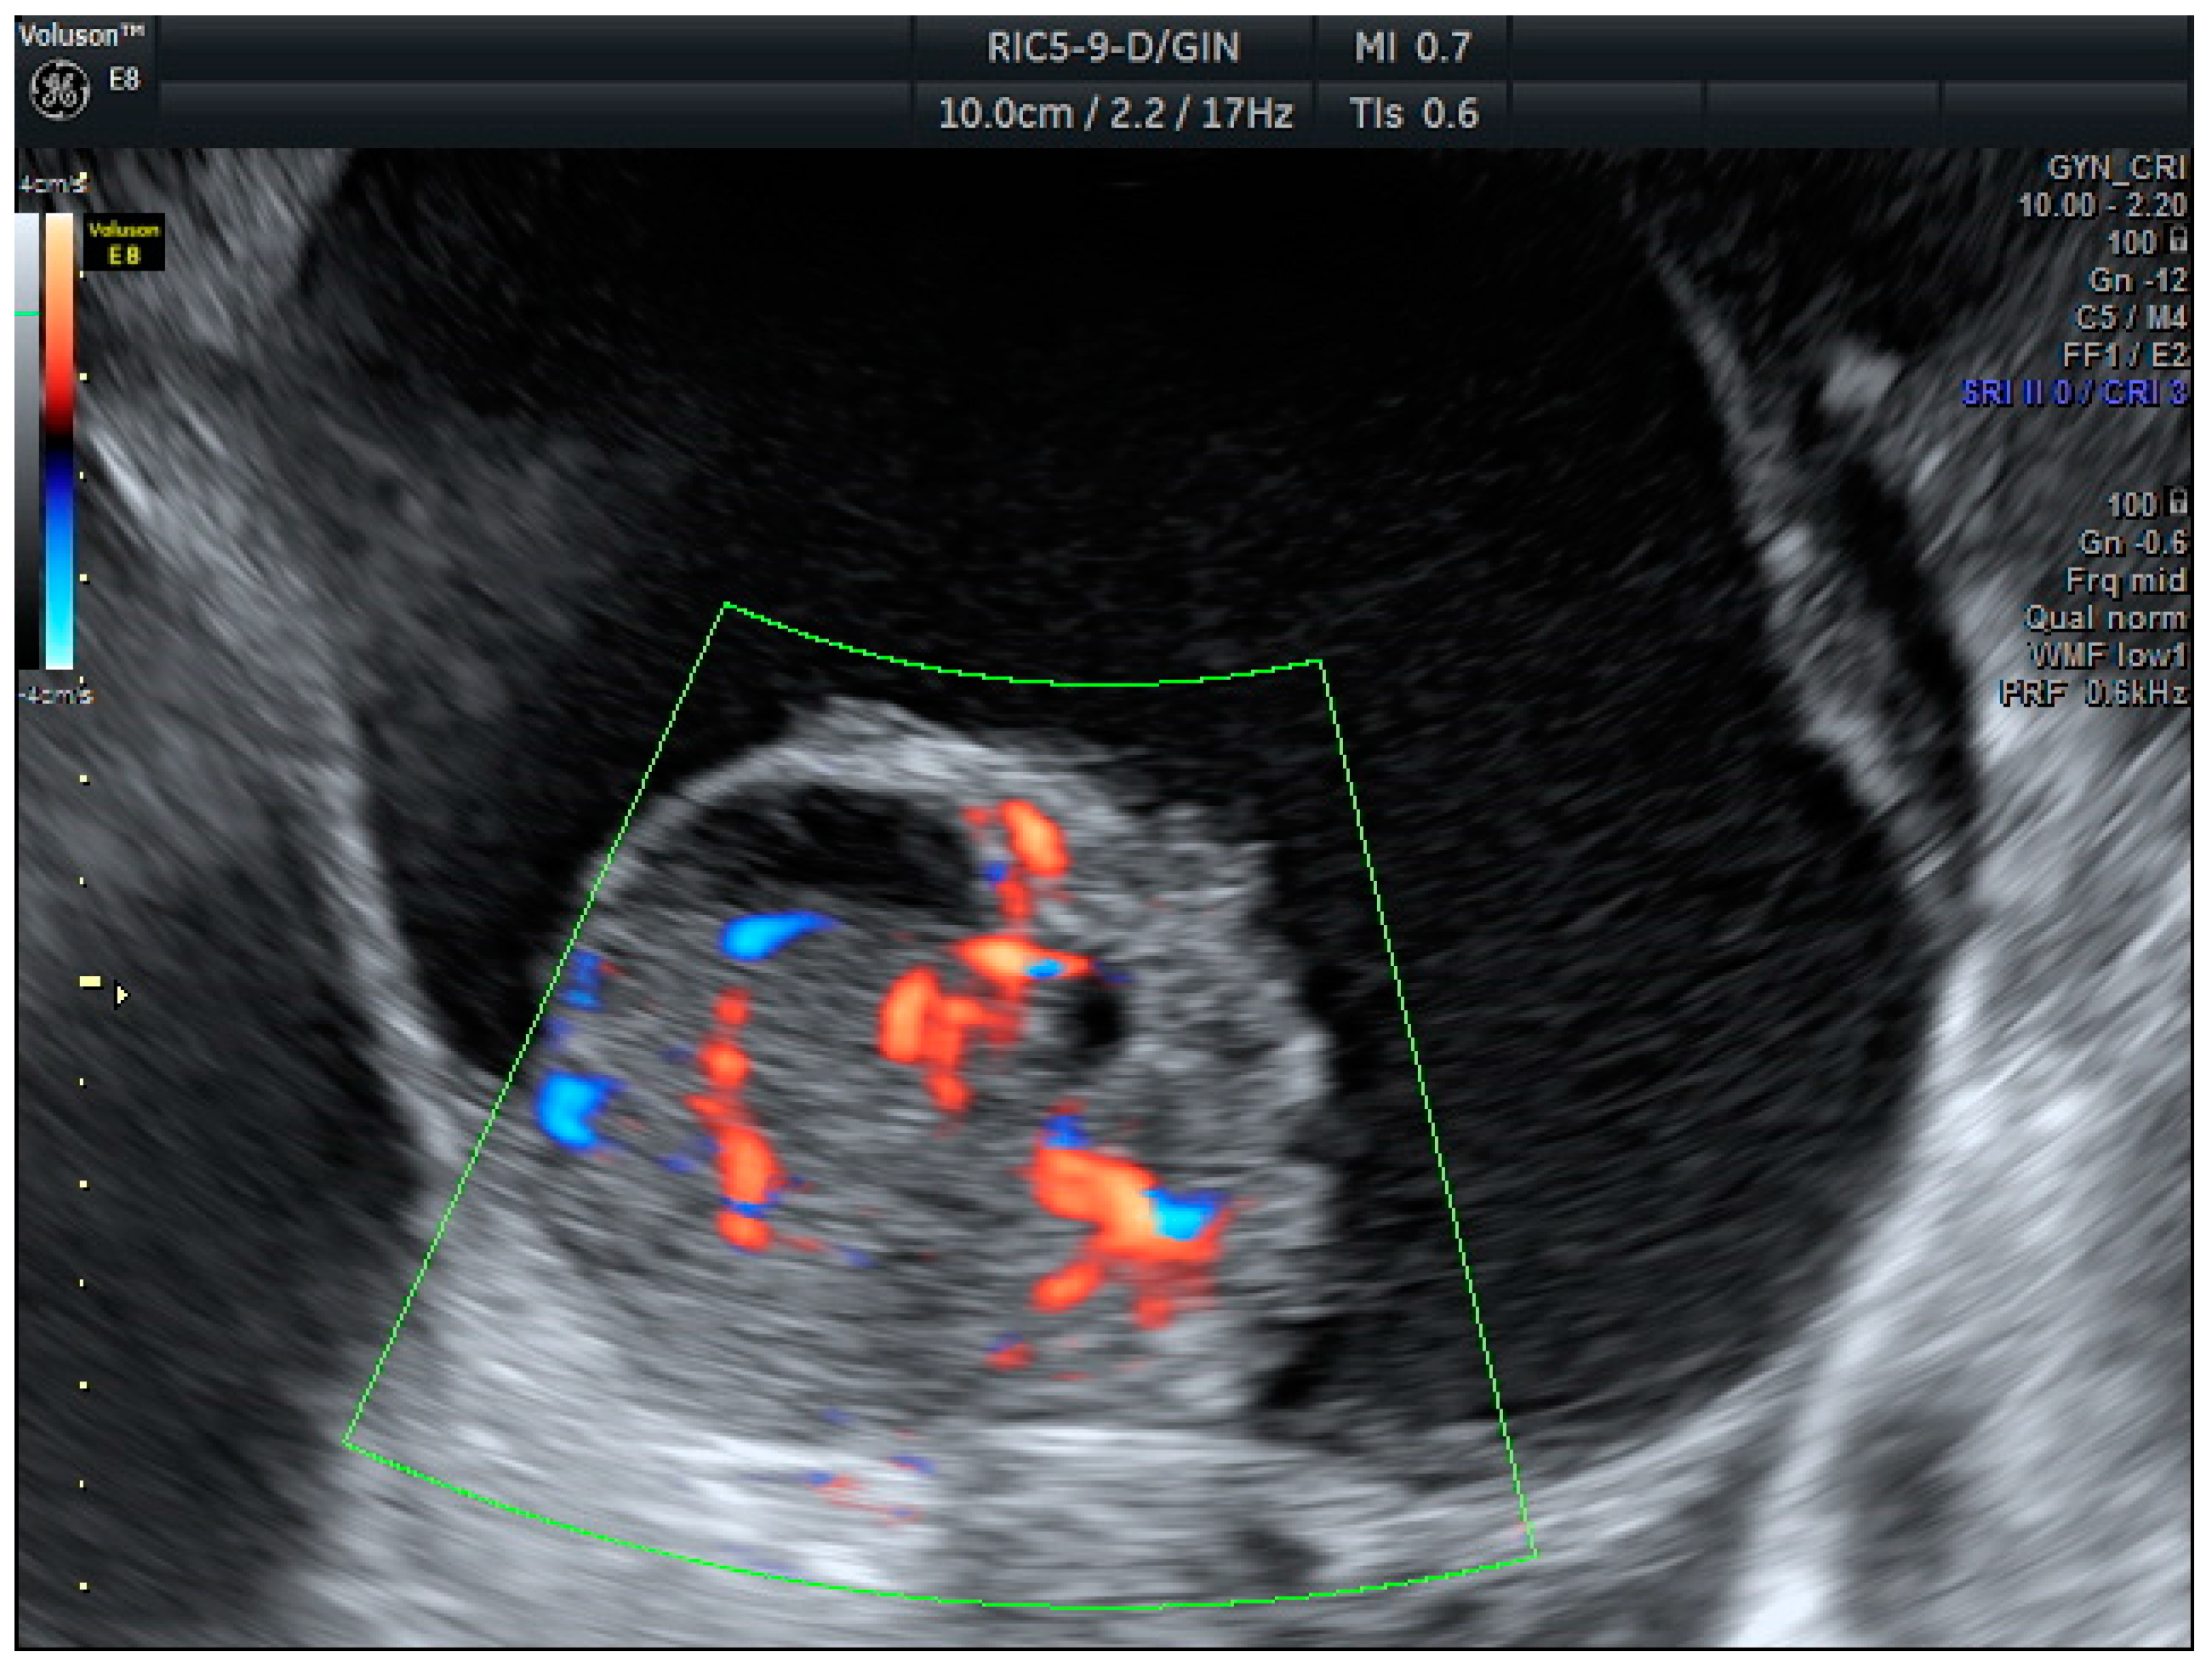

Figure 2.

Serous caricinoma. Multicystic mass with a solid papilla inside with a high score Doppler color (score color 4).